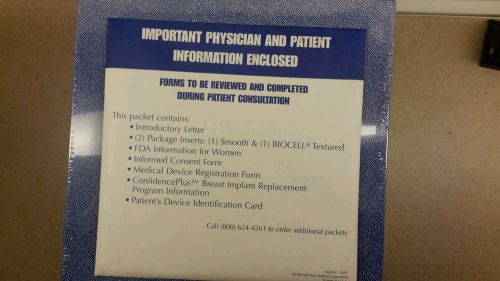

Pair of McGhann Style 468, 495cc Anatomical Saline Breast Implants